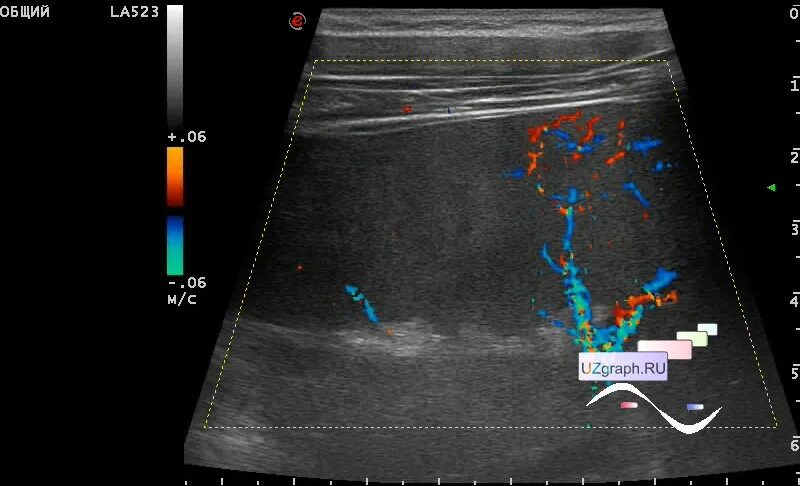

Пульсирующая гематома бедренной артерии на узи. пульсирующая гематома узи. пульсирующая гематома и ложная аневризма. ложная аневризма бедренной артерии на узи.

Пульсирующая гематома узи протокол. пульсирующая гематома узи. пульсирующая гематома бедренной артерии на узи.

Пульсирующая гематома узи. пульсирующая гематома бедренной артерии. постпункционная пульсирующая гематома. гематомы напряженные и пульсирующие.

Аневризма общей бедренной артерии на узи. ложная аневризма бедренной артерии на узи. пульсирующая гематома бедренной артерии на узи. пульсирующая гематома узи.

Пульсирующая гематома бедренной артерии после стентирования. пульсирующая гематома узи. пульсирующая гематома бедренной артерии на узи. пульсирующая гематома узи протокол.